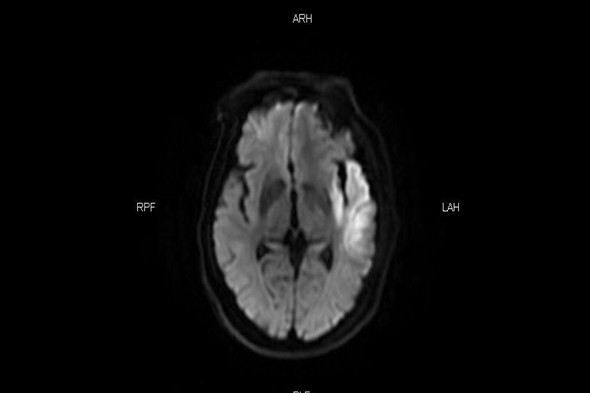

介入科刘琳团队接到通知立即启动脑卒中快速通道,患者准备MR检查的同时介入导管室护士、急诊麻醉师刘洋、赵亮已到位。核磁科崔红升主任团队经过详细的检查分析评估,得出结果为左颈内动脉起始栓塞,颅内小梗塞病灶显影,还有大量可挽救的脑细胞,适合介入取栓治疗挽救患者生命。

DWI 显示小梗塞病灶,还有可挽救的脑细胞